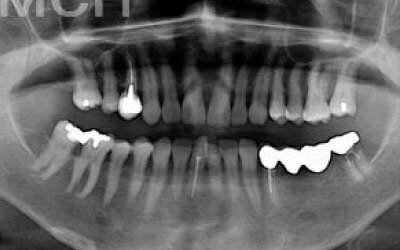

ブリッジ治療では、欠損部分の両側にある歯を大きく削らなければならず、場合によっては虫歯がなくても歯の神経を抜くことがあります。神経を抜いた歯に被せ物をすると、その歯は急速に弱くなり、寿命が短くなるリスクが高まります。

残っている歯にとって、ブリッジ治療は非常にリスクが高い方法です。

その理由は、ブリッジを作るために隣接する歯を大きく削らなければならないからです。

場合によっては、その歯の神経を取ることもあります。それだけ歯に負担をかけるため、歯の寿命が急激に縮んでしまいます。

最も大きな違いは、前後の歯の寿命に影響が出ることです。

ブリッジの場合、抜けた歯の前後にある歯を、重度の虫歯と同じくらいまで削る必要があります。

また、抜けた歯の代わりに前後の歯が力を支えるため、その歯に常に1.5倍の負荷がかかります。

1)ブリッジ

2)歯を大きく削る+支えの歯に1.5倍の力がかかる

3)前後の歯の寿命が著しく減る

ブリッジの支えの歯は、データでは10年以内に68%が抜歯になります。